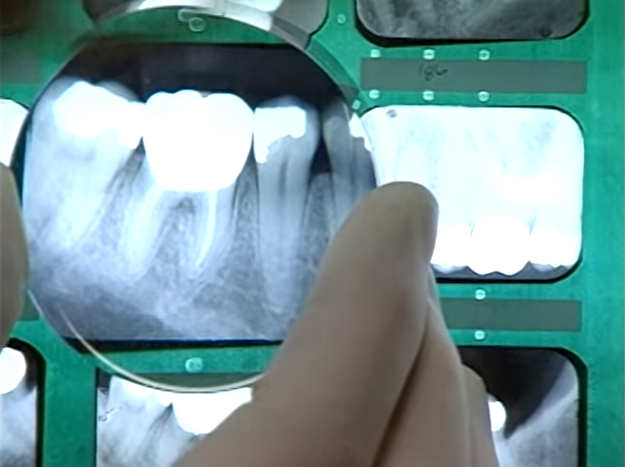

| Hàm răng của nạn nhân vẫn nguyên vẹn. Căn cứ vào hình ảnh X quang, một bác sĩ nha khoa xác định nạn nhân mắc chứng thừa răng (chân của răng thừa hình thành ở phía trước hai răng cửa). Ngoài ra nạn nhân cũng sử dụng nhiều răng giả chất lượng cao. |

| Khi rà soát những trường hợp người mất tích tại Vancouver, cảnh sát chú ý tới Mary-Lynn Breeden, một phụ nữ 31 tuổi có mái tóc vàng. Cô biến mất hôm 6/7/1991, đúng một ngày trước khi cảnh sát phát hiện xác chết cháy trong thùng rác. Hồ sơ nha khoa của Mary-Lynn cho thấy cô cũng có một răng thừa ở phía trước hai răng cửa. Hình ảnh X quang của hai hàm răng trùng khớp với nhau. Cảnh sát đã thấy tia hy vọng đầu tiên trong một vụ án mạng cực kỳ hóc búa. |